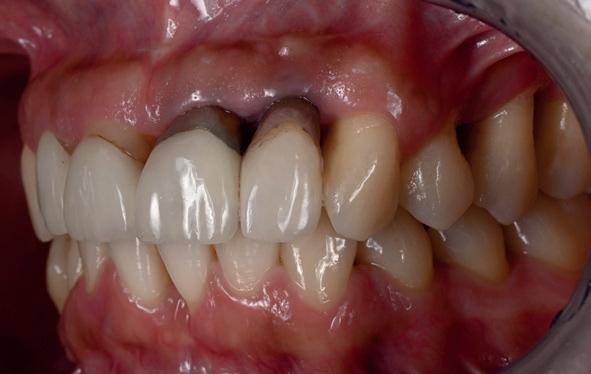

plaatsing van de restauraties werden zowel de tandboog als de tandstand in de bovenkaak gecorrigeerd (afbeelding 13-15).

Aansluitend werd de onderkaak volgens hetzelfde principe gerehabiliteerd, resulterend in een stabiele, functionele en esthetisch gebalanceerde occlusie (afbeelding 16-17).

14. Techniekmodel met restauraties

15. Intra-oraal bovenkaak met restauraties